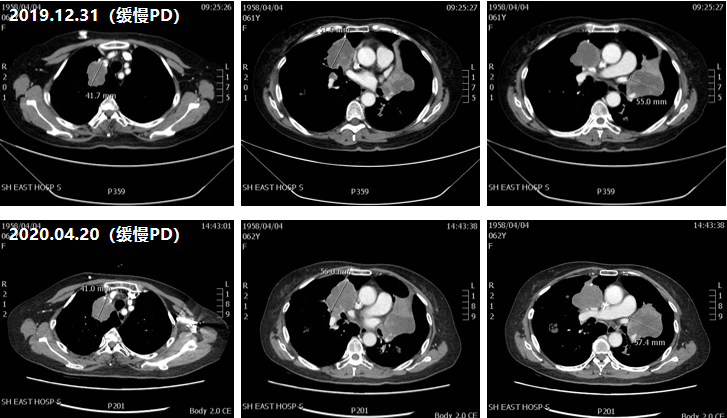

三线治疗(2020年9月-2021年10月)

治疗评估:由于口服靶向单药治疗方案再次出现PD,鉴于既往化疗治疗的有效性,建议患者三线治疗再次选用联合化疗治疗方案;

治疗方案:行贝伐珠单抗联合FOLFOX(奥沙利铂+亚叶酸钙+氟尿嘧啶)方案6周期;

疗效评估:患者在治疗过程中肺部病灶缩小,肝脏病灶保持稳定,直至2021年10月双肺出现多处新发病灶,肝脏病灶出现增大,提示PD;

图3 三线治疗CT影像对比